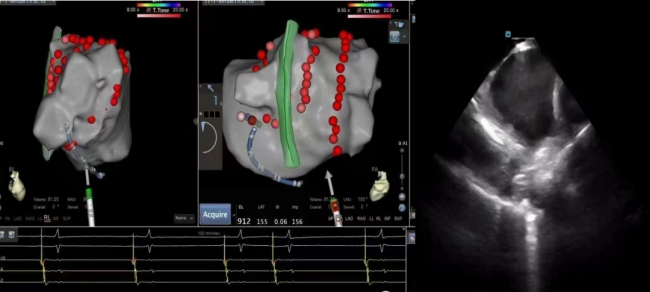

68岁的张先生,因“阵发性房颤、阵发性房扑”就诊于心血管内科,完善相关检查提示心房颤动、心房扑动伴不固定型房室传导阻滞,非特异性ST段异常,具射频消融治疗指征,心血管内科团队经过缜密的术前讨论、方案制定,与患者及家属充分知情沟通后,成功实施ICE辅助下室早导管射频消融术。术后患者恢复窦性心率,未诉特殊不适。我院心血管内科主任、主任医师蒋路平介绍,心腔内超声心动图(ICE)就像是心内科介入医生的“透视眼”,它是指在导管的顶端安置超清超声探头,经外周血管输送至心腔内部,对心脏及其邻近组织进行实时高质量成像和血流动力学测定的超声成像技术,犹如在心脏里长了一双明亮的眼睛一样,可以直观地观察心腔内结构,更清晰、精确定位完成手术,是各种心脏介入手术中重要的辅助工具。该项技术能更直观地显示心腔内结构及实时导管位置,有助于术者更精准快速地进行标测,显著提高了消融的成功率及安全性,减少了手术并发症,缩短了手术时间。心腔内超声心动图(ICE)还能有效运用在“左心耳”封堵术,避免患者术前全麻下食道超声的痛苦,及并发症发生,减少手术费用。

一些需要精准定位的特殊心律失常(如乳头肌室性早搏、希氏束旁室性早搏),通过ICE可以更快更便捷的进行解剖标测。三维心腔内超声能精准定位目标靶点,消融有的放矢,避免累及其他重要结构。

在左心耳封堵手术中,ICE可辅助穿刺,提高封堵手术效率。使封堵器多角度灵活到位,对左心耳开口大小精确测量并进一步释放封堵器,全程可视,提高手术效率,同时降低射线量。对于卵圆孔未闭患者,通过心腔内超声,可直视“隧道”,卵圆孔未闭区清晰可见,封堵器释放过程全程可视,绿色安全。